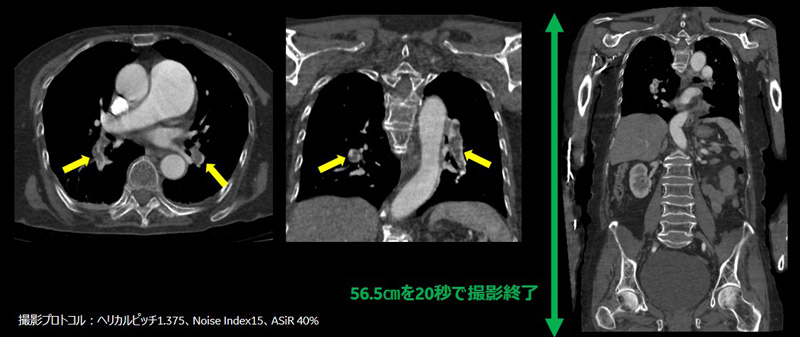

ケース2:肺塞栓症

2,3日前より食事摂取不良、高血圧の既往歴あり。発熱(37.7度)で来院、心電図でSTの上昇があり、また息苦しさを訴えたことから、通常の胸部CT検査のあと、造影検査を追加で実施したところ、肺塞栓症の所見が得られた症例です。肺尖部から骨盤までのスキャン範囲は56.5㎝ですが、約20秒で撮影が終わりました。また、患者が腕上げ困難であったために腕を下ろした状態で撮影を行いましたが、ストリークアーチファクトが抑制された画像であり、画質向上のために工夫したアルゴリズムであることを感じました。